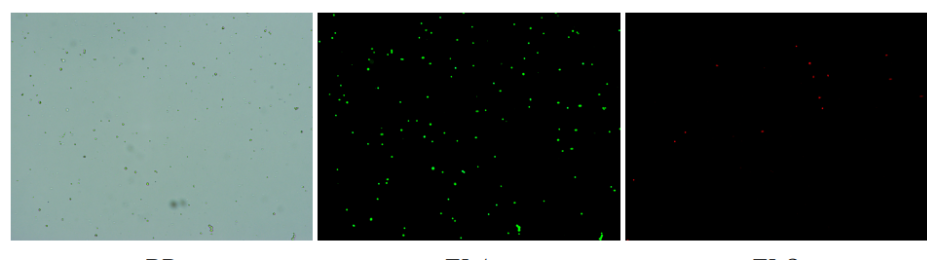

肝臟是人體代謝和解讀的器官,在體內(nèi)發(fā)揮氧化、儲(chǔ)存肝糖、合成分泌性蛋白合成等,肝臟也制造消化系統(tǒng)中之膽汁,人肝約有25億個(gè)肝細(xì)胞。但是解離肝臟組織懸液并不簡(jiǎn)單,首先,肝臟代謝旺盛,離體后肝細(xì)胞無法進(jìn)行正常的有氧糖酵解,細(xì)胞活力會(huì)迅速下降,另外,肝細(xì)胞的線粒體很多,每個(gè)細(xì)胞大約有1000個(gè)左右,遍布于胞質(zhì)內(nèi)。因此,很難得到符合單細(xì)胞測(cè)序要求的單細(xì)胞懸液。百邁客生物在肝臟組織單細(xì)胞懸液制備方面有豐度的實(shí)操經(jīng)驗(yàn),開發(fā)了獨(dú)有的解離體系,下面來看實(shí)驗(yàn)結(jié)果:

實(shí)驗(yàn)結(jié)果

人肝癌樣本,懸液背景干凈,活性91.69%,結(jié)團(tuán)率6%

人膽管癌樣本,活性90.45%,結(jié)團(tuán)率7.2%

Tips: 肝實(shí)質(zhì)細(xì)胞經(jīng)過解離后因?yàn)槿毖醴浅H菀装l(fā)生凋亡,導(dǎo)致占比很低,如果老師關(guān)注肝實(shí)質(zhì)細(xì)胞的話,建議采用單細(xì)胞核懸液的方法。